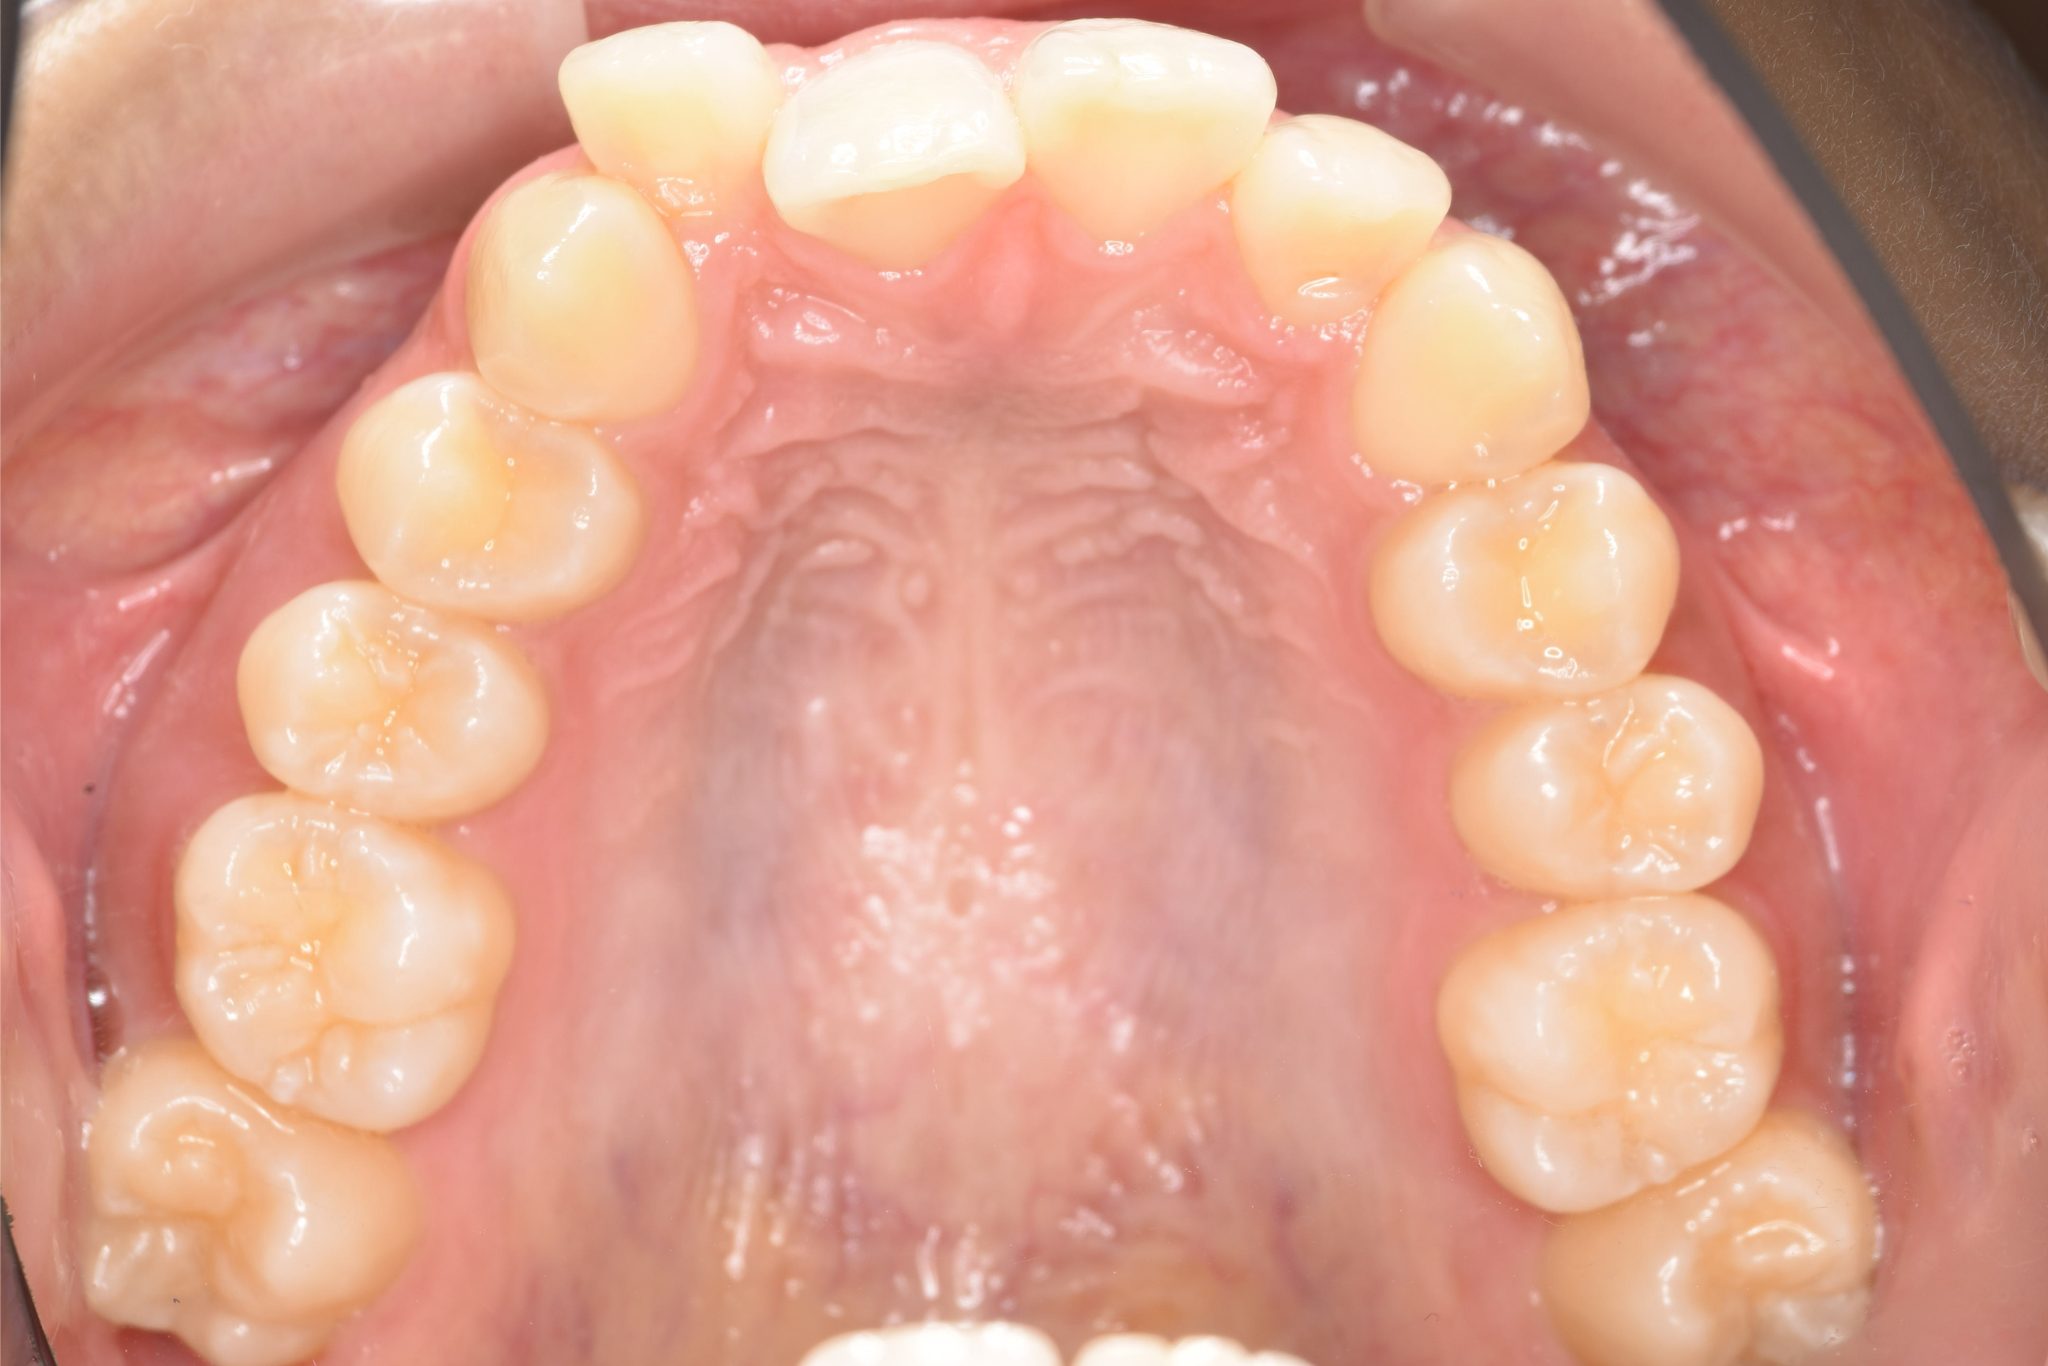

アフター

全顎ワイヤー矯正 症例_418